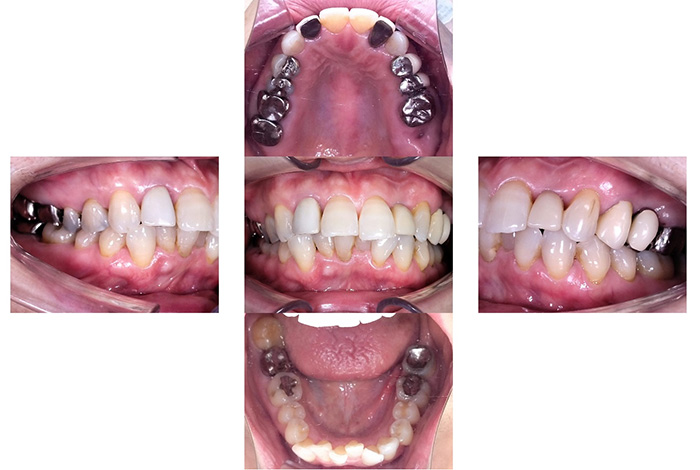

右上臼歯部2本・左下臼歯部2本にインプラント治療を行った症例です。

欠損部に対しインプラントを埋入し、咀嚼機能の回復と咬合バランスの改善を行いました。周囲歯への負担を抑えながら、固定性のある補綴装置により安定した噛み心地を目指した治療です。

欠損部のインプラント治療と金属修復をセラミックへ置き換えた包括的治療症例

患者様は、左下の欠損部の改善と、口腔内にある金属修復物を白い材質に変更したいとのご希望で来院されました。

診査の結果、

が認められました。

機能的回復と審美性の改善の両面から、包括的な治療が必要な状態でした。

以下の治療を行いました。

咬合の回復と審美性の改善を同時に行いました。

本症例では、機能性と審美性のバランスを考慮した材料選択を行っています。

奥歯については、咬合力が強くかかるため、色調よりも強度を優先し、ジルコニアスタンダードを使用しました。

一方で前歯部は、周囲歯との色調調和が重要であるため、より審美性に優れたジルコニアプレミアムを選択しています。

また、欠損部にはインプラント治療を行うことで、周囲の歯に負担をかけずに咬合機能の回復を図っています。

口腔内全体を一つの単位として治療計画を立てることで、機能面・審美面ともにバランスの取れた結果を目指しました。

欠損部の咬合が回復し、奥歯でしっかり噛める状態となりました。

また、金属修復物がセラミックに置き換わることで、口腔内全体の審美性が向上しています。